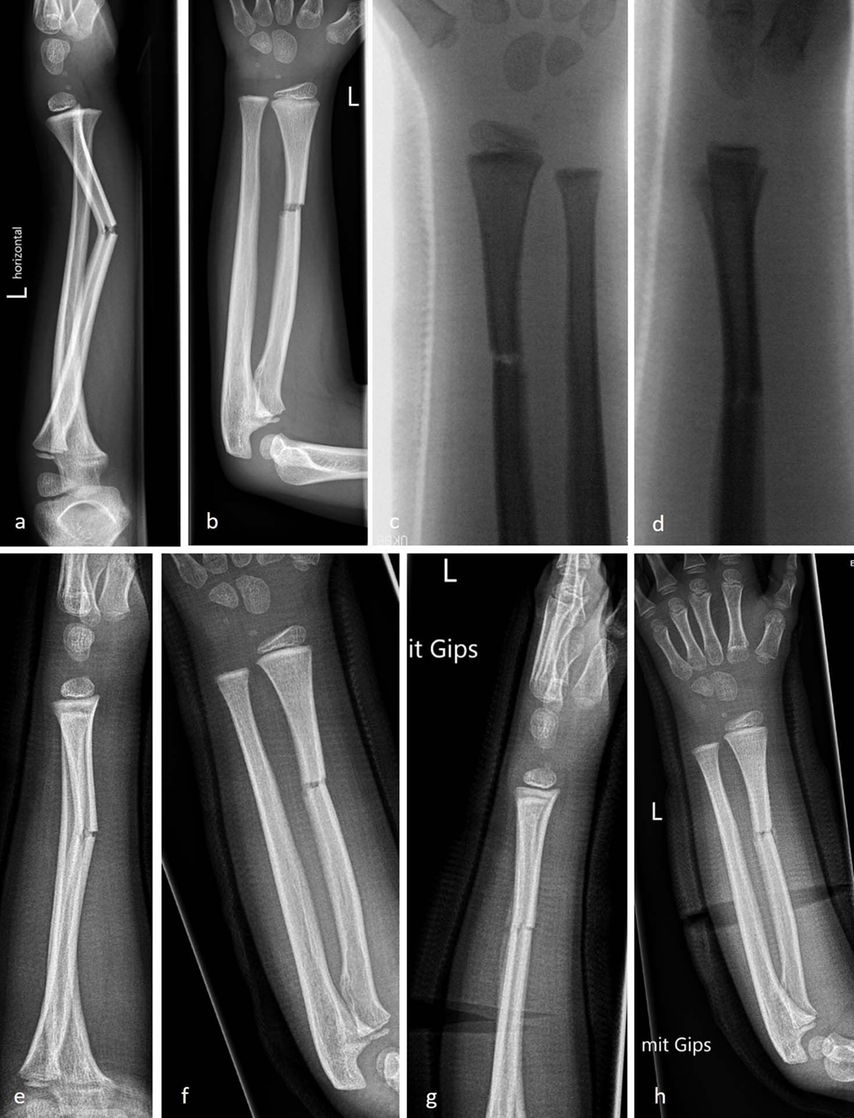

Abb. 9: Fallbeispiel: 6-jähriger Patient mit Radiusschaftfraktur. Unfall (a, b); Reposition (c, d); Stellungskontrolle mit sekundärer Achsabweichung Tag 9 (e, f); Stellungskontrolle 6 Tage nach Keilung (g, h)